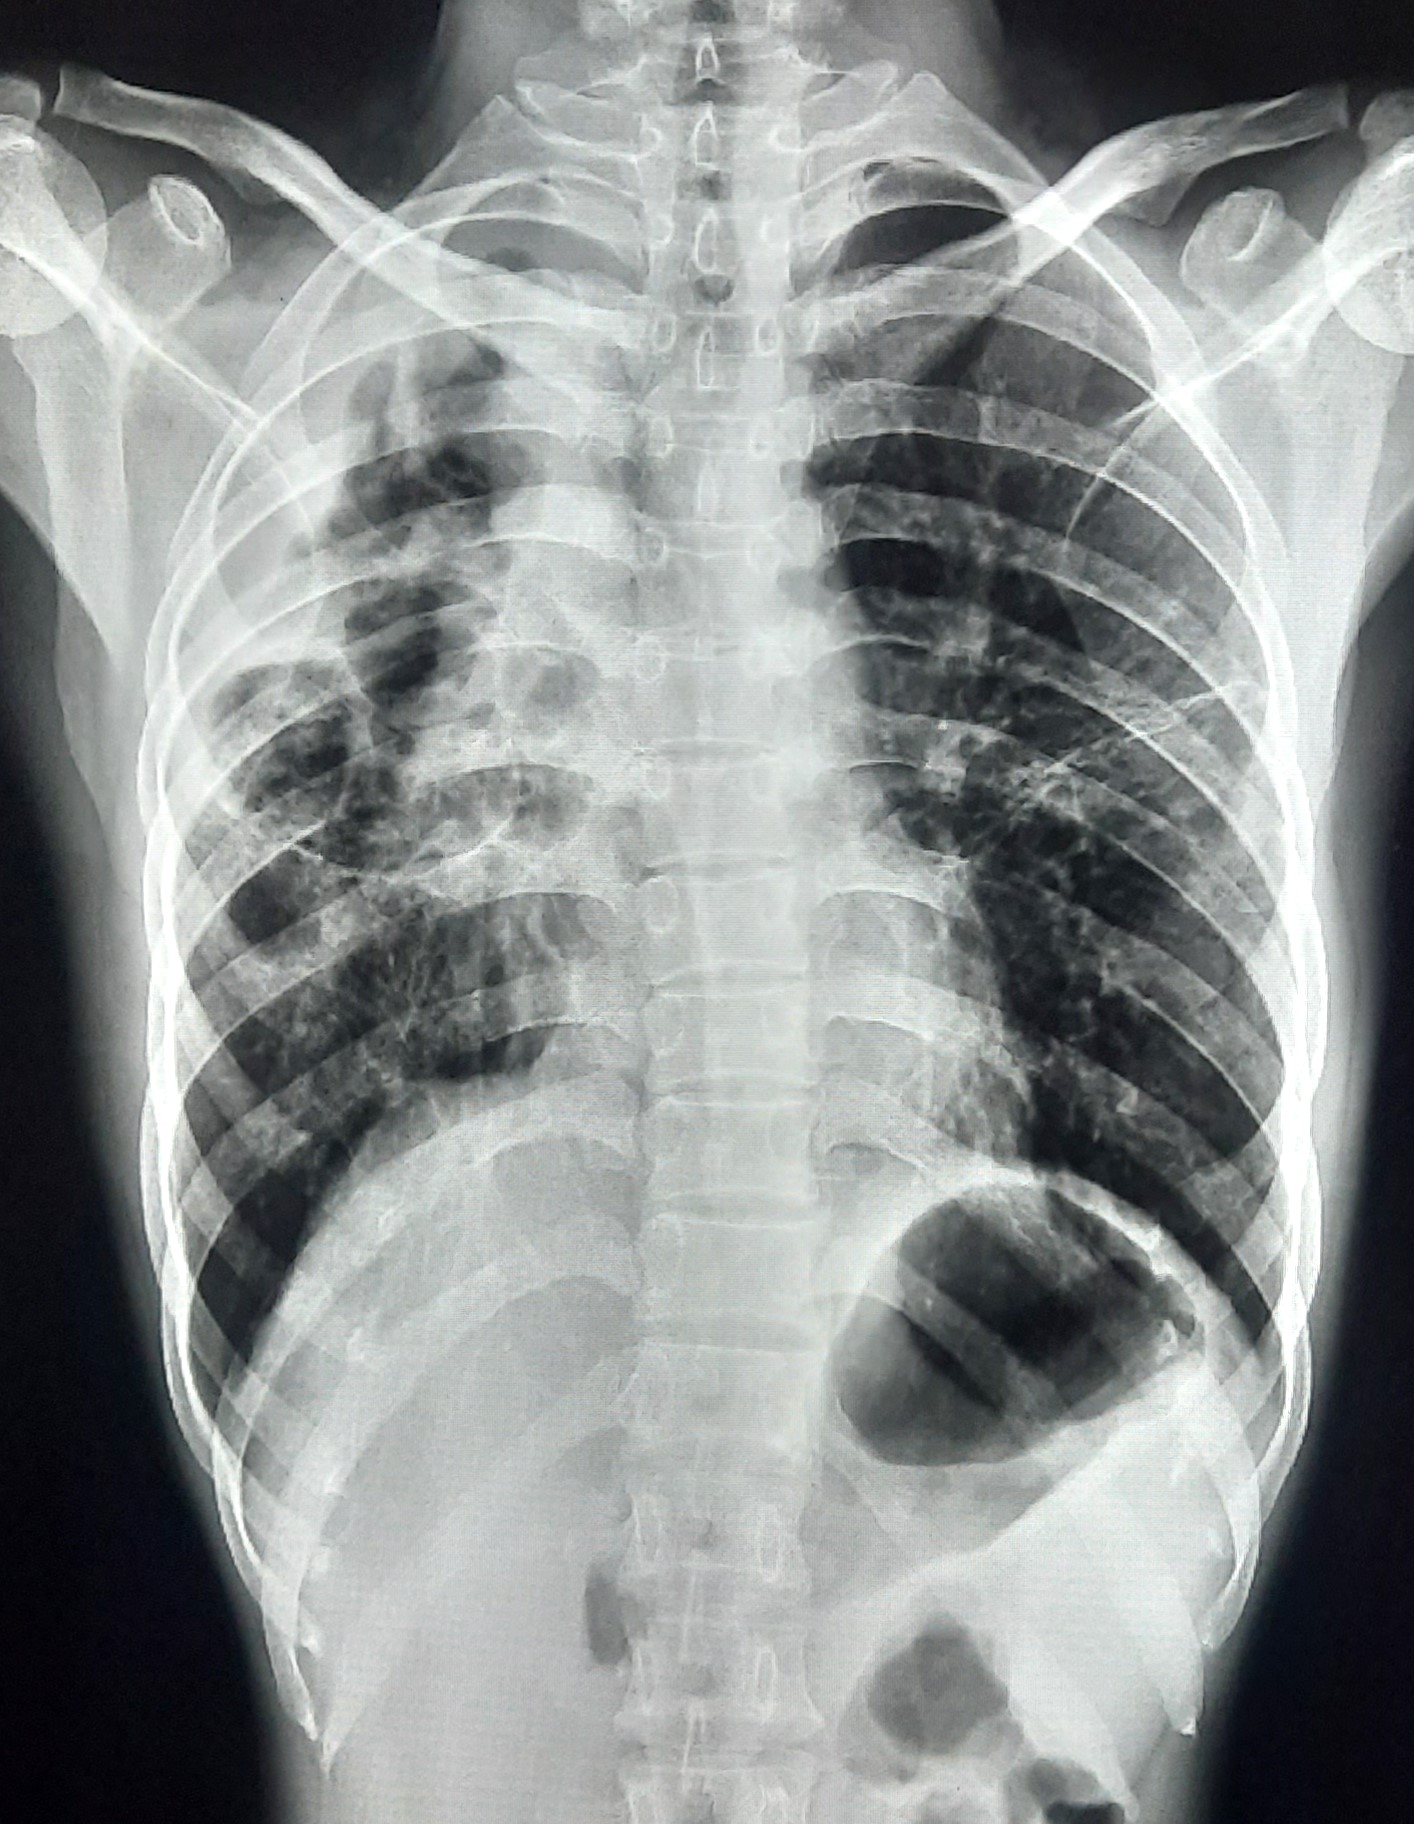

| 127 | IGGMC, Nagpur, Nagpur | P2 | 29-4345 | Hiraman Tembhurne | Consent taken on Paper | 62 Yrs. |

Provisional Diag : Dyspnea

Final Diag : Post TB With Interstitial Lung Disease |

Post TB Sequelae | Bilateral Cystic Opacity Upper, Mid & Lower Zone/ Bilateral Reticular Opacites/ Bilateral Fibrotic Bands Present/ Decrease Lung Volume/ Few Old Calcific Nodules | Abnormality visible on x-ray |